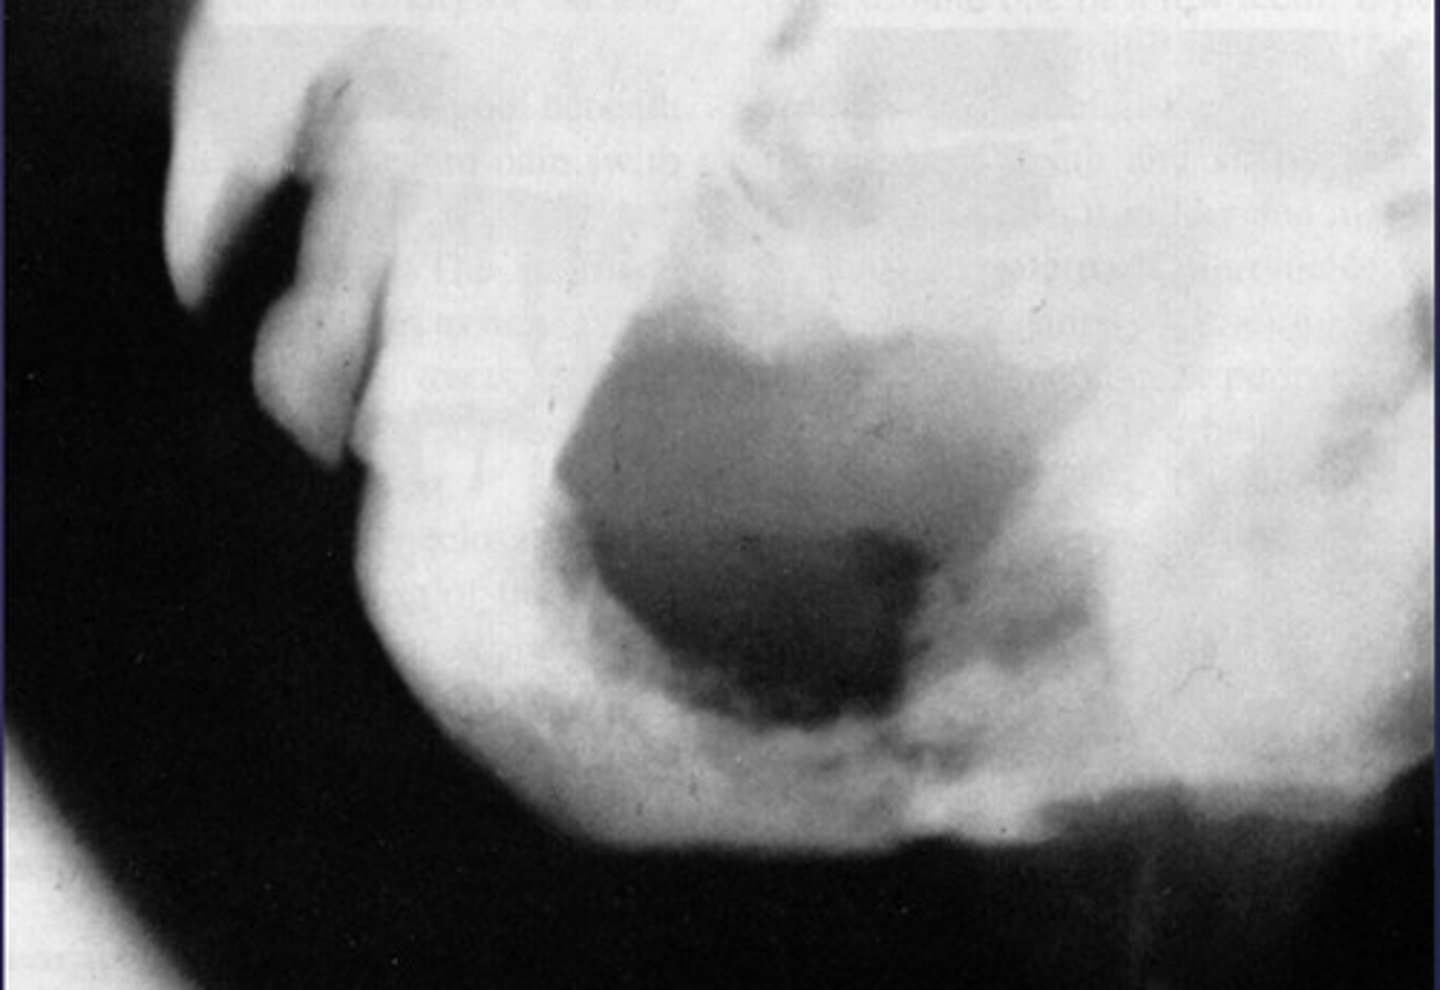

stafne bone cyst

- Located between inferior alveolar nerve canal and inferior border of mandible

- Oval/round/elliptical shape

- Well-circumscribed radiolucency

- Dense sclerotic corticated (radiopaque border) usually on the superior aspect